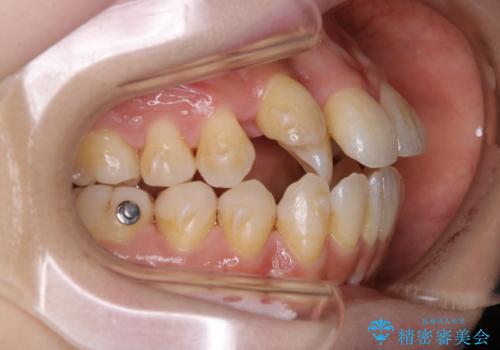

本来は外科ケース:インビザラインで前歯の重度がたつきとオープンバイトの改善

- 前歯のがたつきが気になるとご相談にいらした患者様です。矯正検査の結果、骨格的なズレが大きかったため当初の治療計画では外科矯正をご案内しました。ご本人が手術を望んでおらず、可能な限りの改善を目指すことを目標に治療を開始しました。

元々の骨格的なズレが大きかったため、当初は外科矯正をご提案していました。患者様の強いご希望により、非外科的な処置のみで可及的な改善を目指すことを目標に治療を行いました。以前よりもしっかり噛めるようになり、見た目も劇的に改善したことで大変ご満足いただけました。